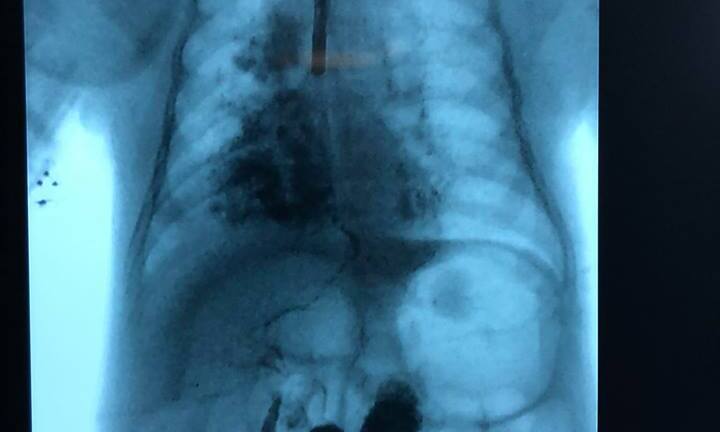

Trường hợp rò khí quản vào đường mật của bé gái rất hiếm gặp, đến nay có chưa đến 40 trường hợp được báo cáo trên y văn thế giới.